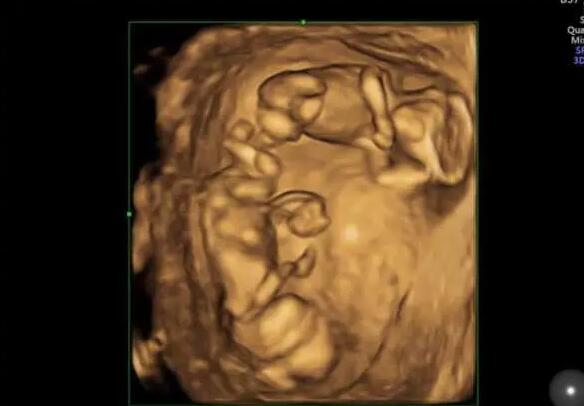

在IVF中,囊胚是胚胎体外培养的终末阶段,它通常形成于卵子受精后的第5-7天。自然状态下,人类胚胎以囊胚的形式植入母体。因此,不难理解,进行囊胚移植,能获得较高的胚胎植入率。